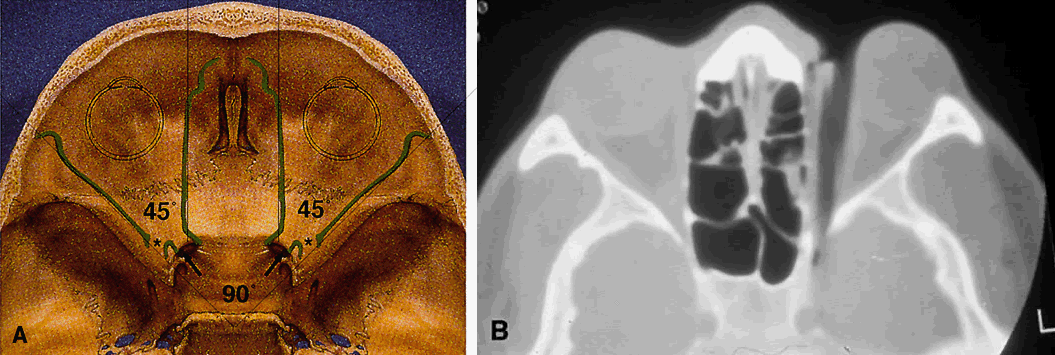

The lesser wing of the sphenoid bone is initially cartilaginous, but the greater wing and the rest of the orbital bones are membranous in nature and ossify and fuse between the 6th and 7th months of gestation. As the orbital bones develop, the eyes converge from an initial 180° relation to their final position of 68°, achieved in infancy. However, the orbital axis remains somewhat divergent at birth (115° between the lateral orbital wall and the skull axis) when compared with that of adults (45°) (Fig. 4).15

Fig. 4. Angular separation of the globes at 2 months' gestation, 3 months' gestation, birth, and adulthood. (Fries PD, Katowitz JA: Congenital craniofacial anomalies of ophthalmic importance. Surv Ophthalmol 35:87, 1990)